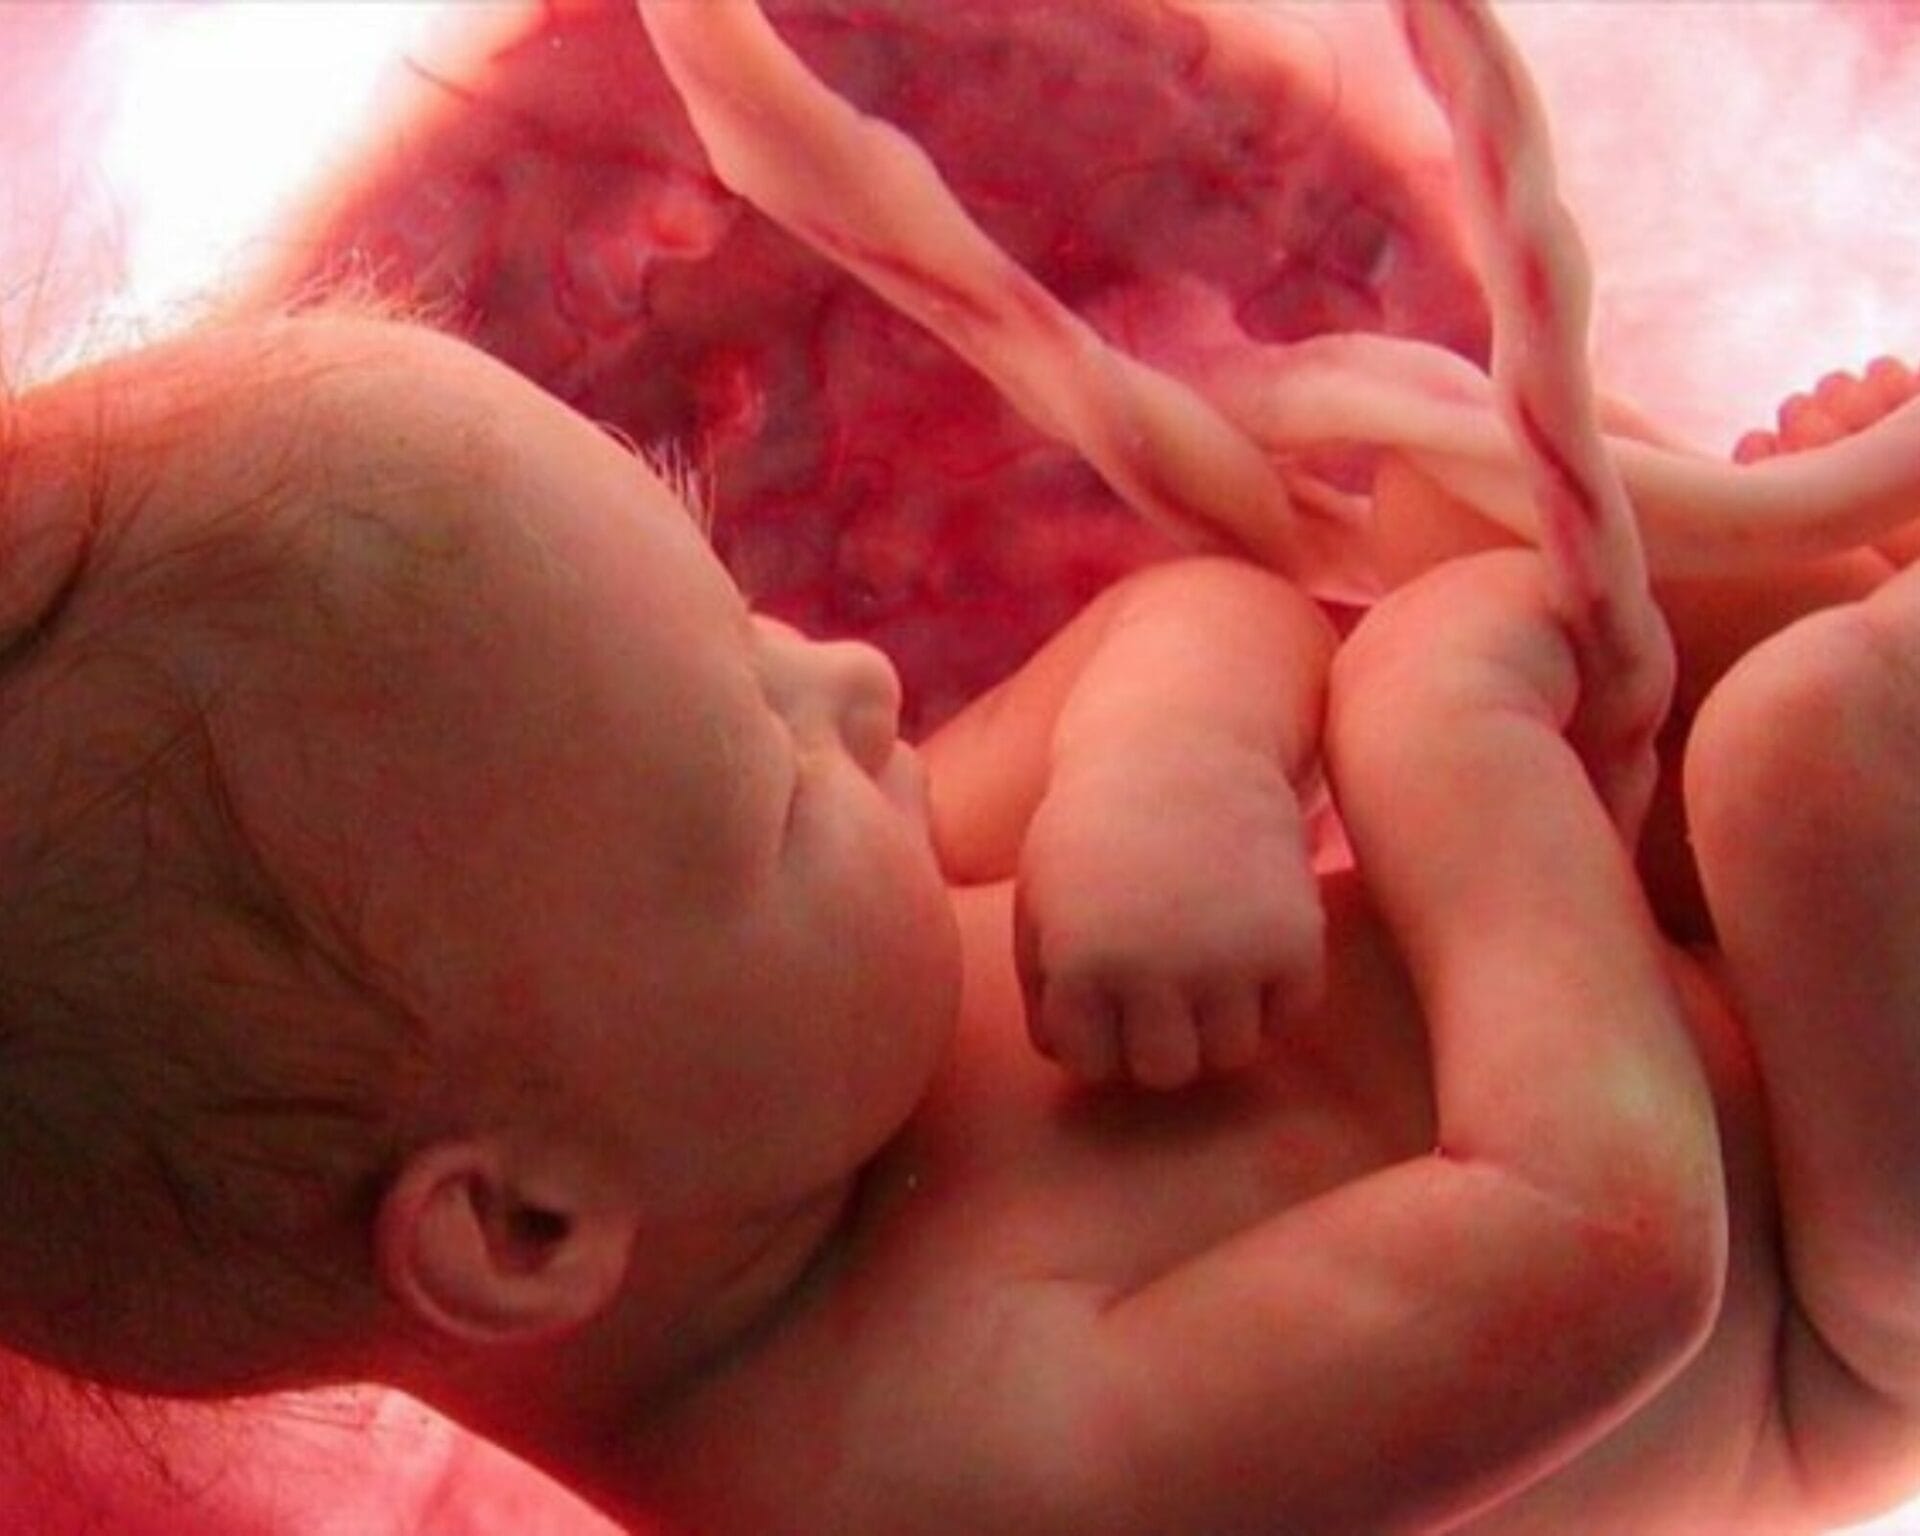

في الأسبوع العشرون من الحمل أصبحت في منتصف الحمل تهانينا أصبح الآن جسده يتناسب مع ذراعيه وساقيه بما في ذلك عينيه وآذانه، بدأ نمو أظافر أصابع يديه وأظافر أصابع القدمين وشعره على فروة رأسه، ويمكنه الآن الاستماع إلى صوت تدفق الدم من حوله، وحركة تنفسك من وإلى رئتيك – وربما أكثر الأصوات المهيمنة، وهو نبض القلب.

جسده بدأ بصنع المايلين، وهي مادة دهنية تغلف وتحمي الأعصاب في جميع أنحاء جسمه حتى تنتقل النبضات الكهربائية من دماغه إلى أطراف أصابع قدميه والعودة مرة أخرى لديه العديد من الخلايا العصبية مثل البالغين الآن، حيث لا تزال الأعصاب الموجودة في دماغه والتي تتحكم في الحواس تتشكل الآن وهي الرائحة والنظر والسمع والتذوق واللمس على الرغم من أن رئتي طفلك لم تتطور بعد بشكل كافٍ.

اللانجو عبارة الشعر الناعم الذي يغطي جلد الطفل،